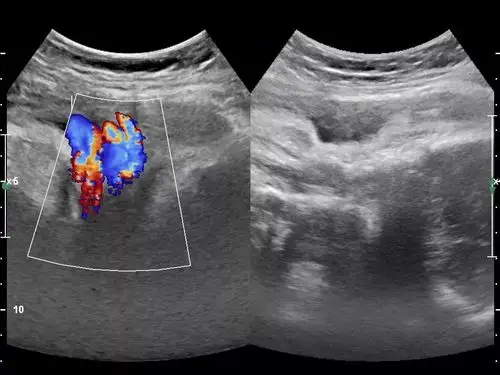

典型的胎儿脐带绕颈检查过程中下滑了——zengerya - 超声医学讨论版

典型脐带绕颈(2周) - 超声医学讨论版 - 爱爱医医学论坛

超声诊断脐带缠绕

胎儿脐带绕颈及唇部欣赏 - 超声医学讨论版 - 爱爱医医学论坛